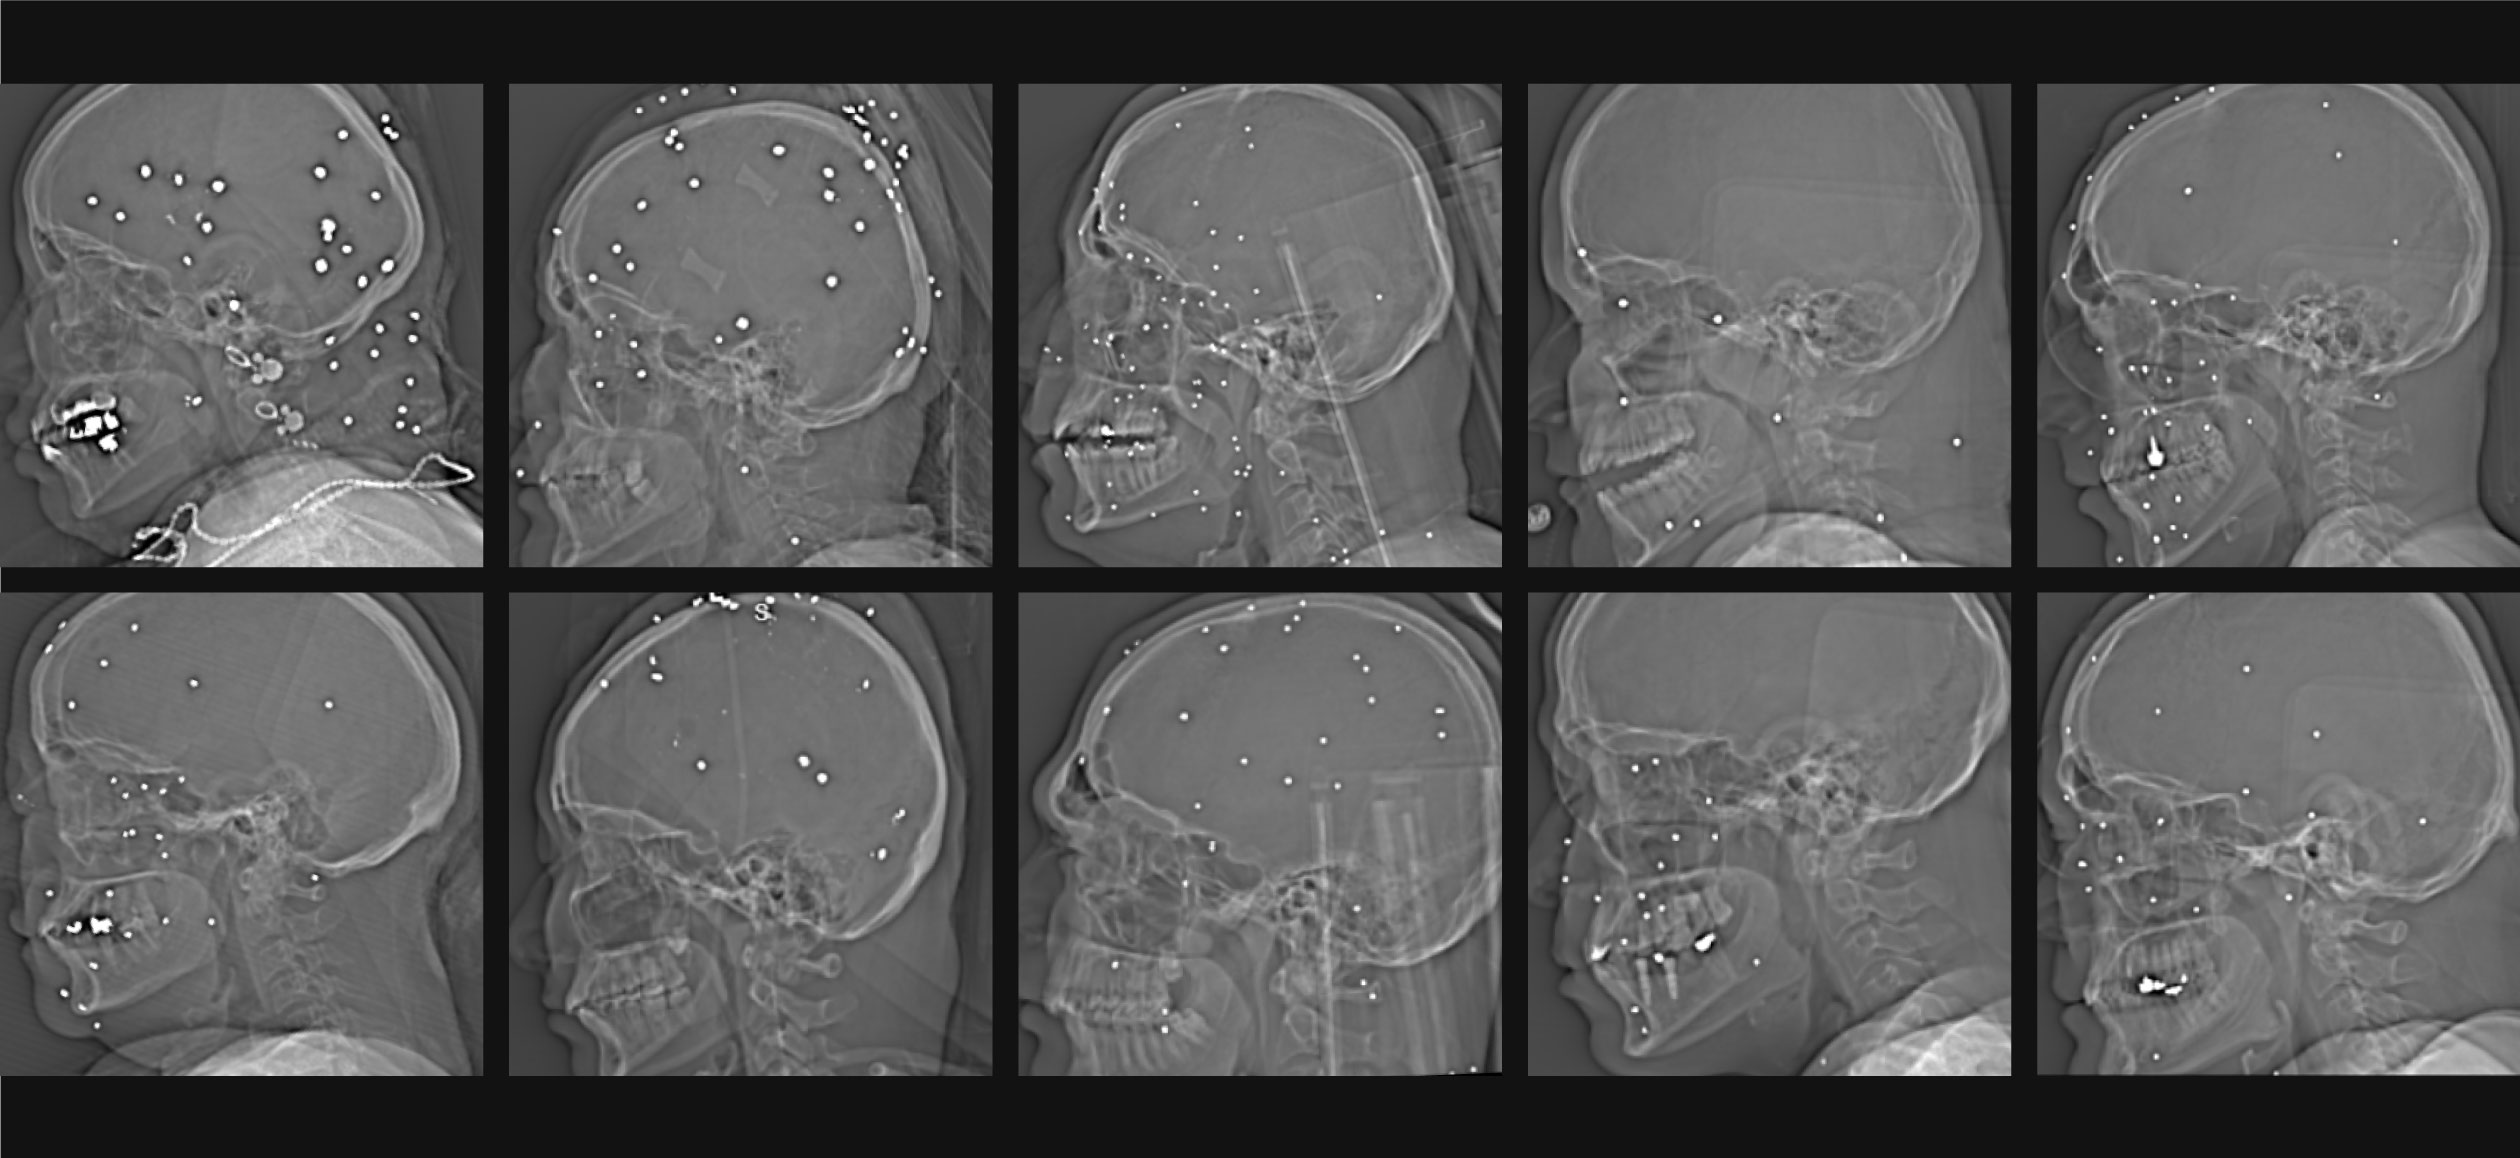

Британська газета опублікувала матеріал щодо застосування дробовиків проти цивільних під час протестів в Ірані. Журналістам передали понад 75 рентгенівських знімків із лікарні в одному з великих міст. Як стверджується, їх зробили за одну ніч у січні.

На знімках спостерігаються численні металеві кульки діаметром 3–5 мм в очницях, обличчі, шиї, грудній клітці та голові. Одна з постраждалих — жінка близько 20 років — вижила, але втратила щонайменше одне око.

Згідно з аналізом видання, 29 із 75 постраждалих зазнали поранення в обличчя, щонайменше дев’ятеро — в ділянку таза та геніталій. Один із іранських лікарів повідомив, що серед поранених були особирізного віку. Влада Ірану ситуацію публічно не коментувала.